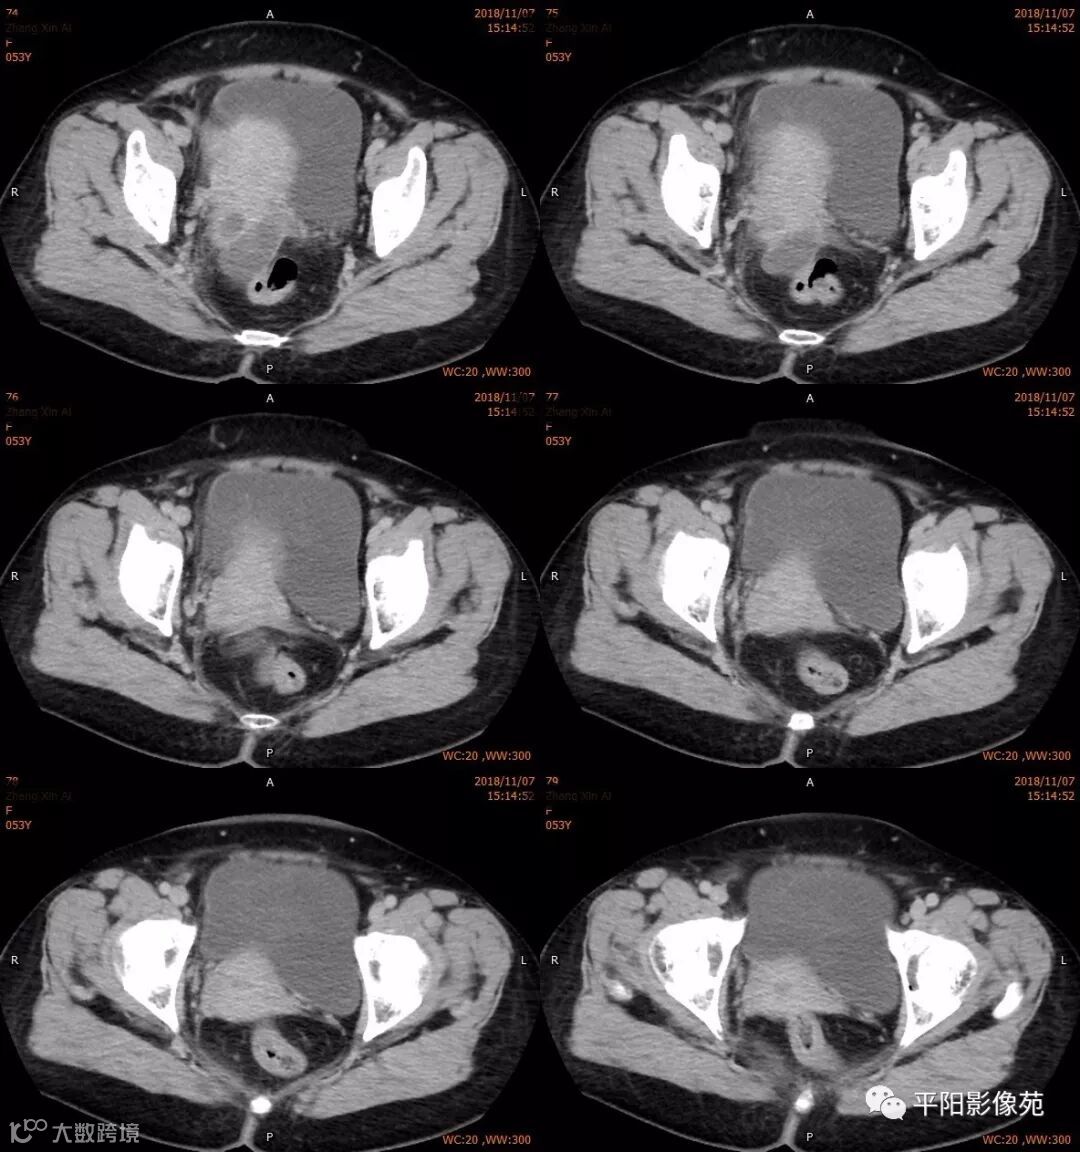

影像特点

右附件区薄壁囊性病变,壁明显强化,边界不清,供血动脉源自子宫动脉,且局部动脉血管增多;其内侧可见卵圆形无强化囊性病灶。

附件区病变多见于卵巢,以囊性为主的病灶多为卵巢囊肿、粘液/浆液性囊腺瘤、皮样囊肿等,这些病灶都具有鲜明瘤体结构,且壁强化多为轻-中度,供血动脉多源自卵巢动脉;而本例患者右附件区薄壁囊性病灶,多位置观察形态为迂曲管状,且壁有明显延迟强化,供血动脉源自子宫动脉,较对侧血管丰富,故而考虑源自输卵管或子宫病变,但子宫发生的薄壁囊性病变较少,多见于子宫肌瘤囊变,完全囊变者少见,且形态轮廓与肌瘤相同为球形故而排除,结合患者腹痛前有感冒病史,且有压痛,因此考虑输卵管积脓可能。其内侧无强化囊性肿块,考虑卵巢囊肿可能。

附件区局限性囊性低密度灶,壁厚,均匀强化,脓腔不强化,若病灶内有气体存在更支持积脓。